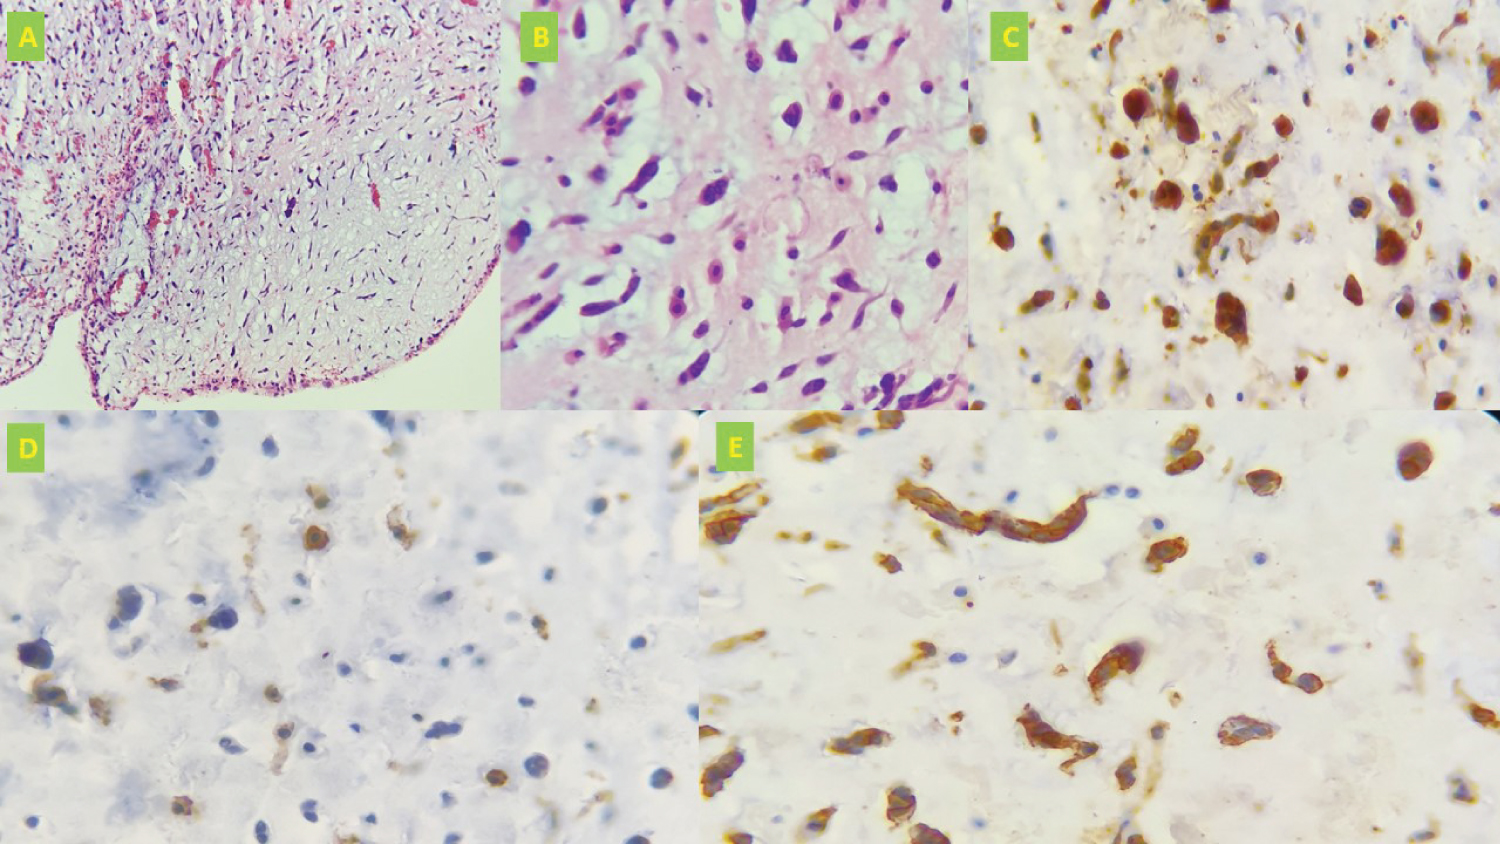

We present a 10-year-old female, who six months prior to consulting began experiencing general symptoms consisting of fatigue, weakness, poor exercise tolerance, weight loss, intermittent fever of 39 °C, progressive dyspnea and syncope with mild exertion in the last 30 days. She was referred to our cardiovascular center due to suspected bacterial endocarditis. On physical exam, she weighed 21 kg, had a height of 138 cm, a body mass index (BMI) of 11 kg/m2, and a heart rate of 95 beats per minute. She had an increased left parasternal impulse, with increased intensity of the first sound, a normal second heart sound, a holodiastolic murmur and a systolic murmur radiating to the anterior axillary line. Her peripheral pulses were normal. She had multiple nevi on her face and a blue nevus on the top of her left foot. She had no significant family medical history. An electrocardiogram showed sinus tachycardia, and the chest X-ray was normal. A transthoracic echocardiogram showed a cardiac tumor with irregular borders adhered to the left side of the interatrial septum, with a tumor area of 10.8 × 13.8 cm2. There was diastolic prolapse into the inflow tract as far as the trabeculated portion of the left ventricle (LV), causing obstruction of the mitral valve (MV) and LV outflow tract (Figure 1). In addition, there was moderate eccentric mitral regurgitation (MR) and left atrial (LA) dilation. The MV leaflets and subvalvular apparatus were normal. No other affected valves, or tumors at other sites, were found. Pulmonary pressure and LV function were normal. The labs showed a hemoglobin of 7.5 g/dl, normal leukocytes and platelets, and negative inflammatory markers and blood cultures. She underwent surgery with partial resection of the interatrial septum, complete transeptal tumor resection, and interatrial septum reconstruction with an autologous pericardial patch, with no complications. The anatomic pathology exam showed a tumor with irregular borders, weighing 23 grams and measuring 6 × 6 × 2 cm, with a myxoid appearance, soft consistency, light color and hemorrhagic and congestive areas (Figure 2). Microscopic examination revealed a neoplasm formed by elongated cells with scant, poorly defined cytoplasm and oval and fusiform nuclei, within a myxoid, vascularized and hemorrhagic stroma (Figure 3). Calretinin, factor XIIIa, CD31, CD34 and vimentin immunohistochemical markers were positive (confirming a myxoma). The differential diagnosis included chronic inflammatory processes or metastatic carcinomas, which were ruled out by negative CD68 and cytokeratin (CK) immunohistochemical markers.

Figure 3: Microscopic anatomic study (A) Hematoxylin-eosin coloration, 10X magnification, showing vascularized myxoid stroma and elongated neoplastic cells with eosinophilic cytoplasm and ovoid nuclei; (B) 40X magnification showing sparse eosinophilic cytoplasm and nuclei with homogeneous chromatin; (C) Immunohistochemical markers (nuclear and cytoplasmic calretinin positive); (D) Immunohistochemical markers (CD31 positive); (E) Immunohistochemical markers (CD34 positive). View Figure 3